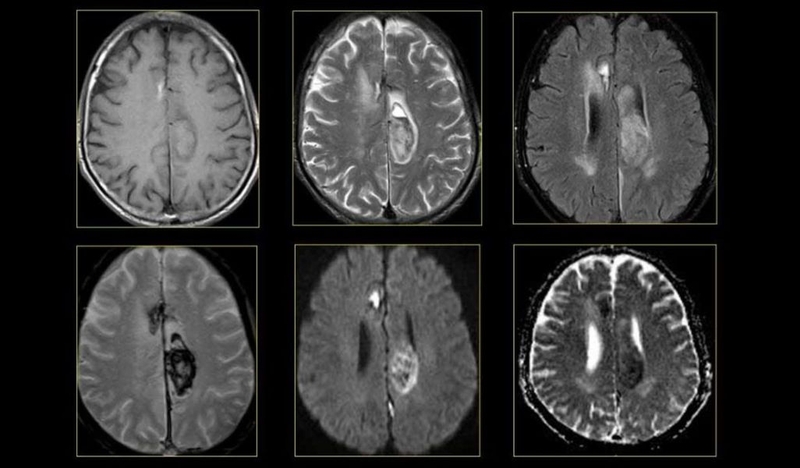

Chụp cộng hưởng từ (MRI): Biện pháp này sử dụng nam châm và sóng vô tuyến mạnh để có thể tạo ra hình ảnh chi tiết về não bộ người bệnh. Hình ảnh chụp sẽ chi tiết hơn về các mô não có liên quan đến nguyên nhân bị dị dạng mạch máu não, từ đó cung cấp thông tin chi tiết cho bác sĩ về vị trí chính xác của dị tật hoặc bất kỳ chi tiết nào liên quan đến dị dạng mạch máu não.